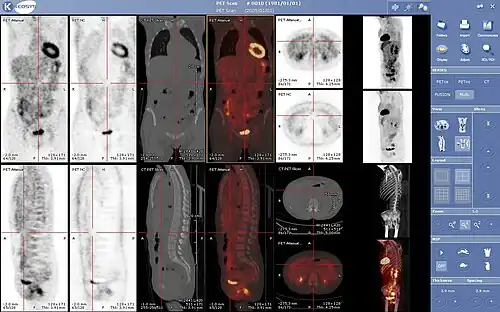

Ce n'est qu'à partir des années 2000 que les premiers scanners multi modalité TEP/TDM couplant au sein du même statif un scanner à rayons X (tomodensitométrie, TDM) avec un scanner TEP sont construits puis commercialisés[5]. Ces machines sont dorénavant le standard de référence, les grands constructeurs (Philips, Siemens et GE) ne fabriquent plus que ce type de machine et la quasi-totalité des services cliniques utilisent des machines multi-modalité TEP/TDM.

Il est possible d’améliorer la qualité des images en utilisant le principe de correction d’atténuation. Lors de la traversée du corps, de nombreux photons gamma subissent une atténuation liée aux structures traversées et à leur épaisseur. En effet, un foyer hyperfixant situé en profondeur sera moins visible qu'un même foyer situé en surface. Pour effectuer cette correction, on utilisait initialement des images de transmission obtenues grâce à une source radioactive qui tourne rapidement autour du patient. Cependant la plupart des caméras TEP sont aujourd'hui couplées à un tomodensitomètre à rayons X (système TEP/TDM ou PET/CT en anglais), ce qui permet de superposer l'image fonctionnelle (image TEP) à sa localisation anatomique précise dans le corps (image CT). La correction d’atténuation ainsi réalisée permet d'effectuer l'examen beaucoup plus rapidement et d'obtenir des images de meilleure qualité.